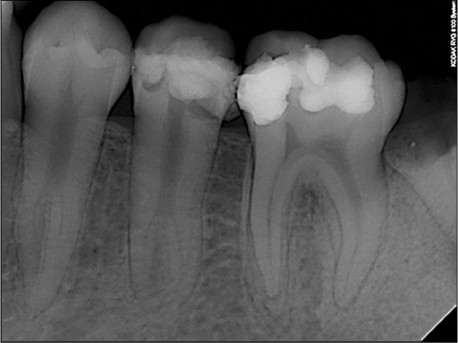

20. (Select ONE OR MORE correct answers.)

Which of the following may complicate the root canal treatment on tooth 3.6?

21. (Select ONE OR MORE correct answers.)

Which of the following may complicate the root canal treatment on tooth 2.6?